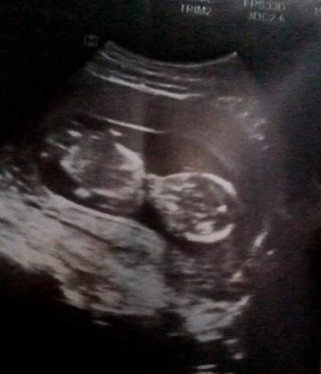

เพื่อนรุ่นน้องซาวด์ตอน 13 วีค ท้องได้ 3เดือนกว่าคุณหมอบอกว่าลูกดิ้นแล้วเเต่ทำไมคุณเเม่ไม่รู้สึกเลย หรือเป็นเพราะขนาดตัวลูกยังเล็กมาก เเละอย่างนี้ลูกผิดปกติไหมค่ะ